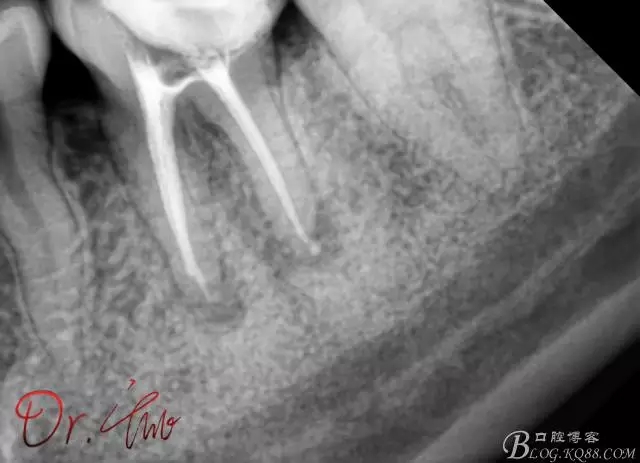

試主尖,近中頰側(cè)試主尖,此時(shí)手用銼02錐度的已擴(kuò)到30號(hào),可以明顯感覺到臺(tái)階位置,挫預(yù)彎后找好正確位置可順利到達(dá)根尖,但是機(jī)用銼就是下不去,也是郁悶

640.webp (9).jpg

試主尖,在30號(hào)02錐度K挫到達(dá)根尖后,用02錐度牙膠尖找準(zhǔn)位置,進(jìn)行試尖

640.webp (10).jpg

最后根充,明顯可看到臺(tái)階位置,期待預(yù)后效果

640.webp (11).jpg